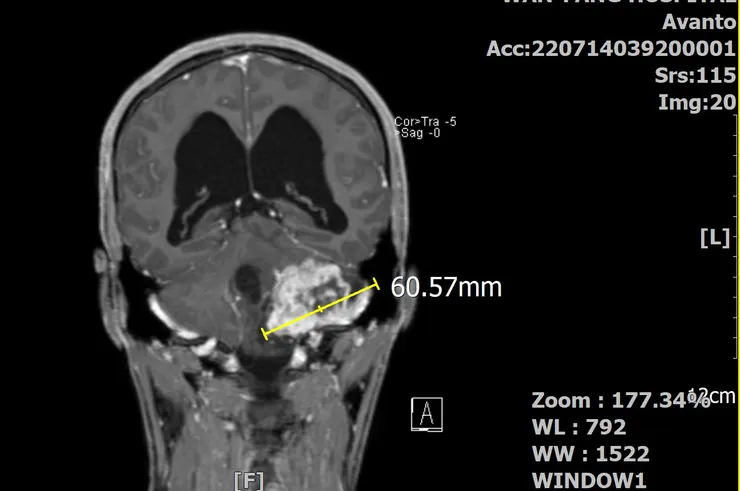

椰當年在MRI下的龐大身軀(冠狀剖面)

當時的椰已經6公分了,這體積早把我的腦幹都「擠歪」了。影響最的的是聽力跟平衡的狀況,於是我逐漸失去了左耳的聽力,以及走在亂石堆的郊山步道上,總是很怕跌倒(不是體力差)。